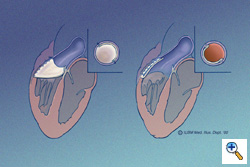

A bullet-shaped piece of 0.1-mm PTFE (Preclude® pericardial membrane, W.L. Gore & Associates, Flagstaff, AZ) is fashioned as shown. The membrane is placed in the ventricular portion of the opening, allowing it to lay flush along the ventricular walls and conal septum, thereby maximizing surface area coaptation. The edges of the PTFE are traced with a marking pen according to their point of contact with the epicardial surface and the material is cut to the dimensions as outlined. This complements the RVOT anatomic geometry. The illustration on the left shows a short RVOT incision, the illustration on the right shows an extended RVOT incision. The monocusp must be longer, obviously, for a patient with a longer ventriculotomy. This is a key technical point. The monocusp is not constructed to approximate the size of the remaining pulmonary valve leaflets, it is constructed to approximate the size of the ventriculotomy opening. The leading edge of the proposed monocusp is actually flat. It appears curved in these illustrations to show the depth of the leading edge when it fills the RVOT.

A bullet-shaped piece of 0.1-mm PTFE (Preclude® pericardial membrane, W.L. Gore & Associates, Flagstaff, AZ) is fashioned as shown. The membrane is placed in the ventricular portion of the opening, allowing it to lay flush along the ventricular walls and conal septum, thereby maximizing surface area coaptation. The edges of the PTFE are traced with a marking pen according to their point of contact with the epicardial surface and the material is cut to the dimensions as outlined. This complements the RVOT anatomic geometry. The illustration on the left shows a short RVOT incision, the illustration on the right shows an extended RVOT incision. The monocusp must be longer, obviously, for a patient with a longer ventriculotomy. This is a key technical point. The monocusp is not constructed to approximate the size of the remaining pulmonary valve leaflets, it is constructed to approximate the size of the ventriculotomy opening. The leading edge of the proposed monocusp is actually flat. It appears curved in these illustrations to show the depth of the leading edge when it fills the RVOT.